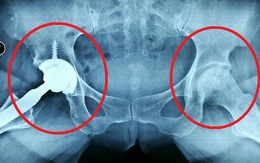

Tác hại kinh khủng của rượu khiến người uống hoại tử 2 chỏm xương đùi

Một người đàn ông bị hoại tử 2 chỏm xương đùi, phải phẫu thuật thay khớp háng vì uống rượu liên tục trong nhiều năm. Đây là bài học đắt giá cho các quý ông hay "thèm" rượu.